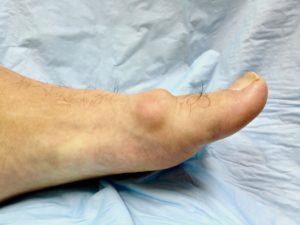

As the condition progresses, the body lays down additional bone around the joint margins, which restricts the movement and can obliterate it all together. As the arthritis in the joint gets worse, as shown in the picture below, the treatment options change. In severe cases, conservative care can be less helpful and it is often difficult to save the joint.